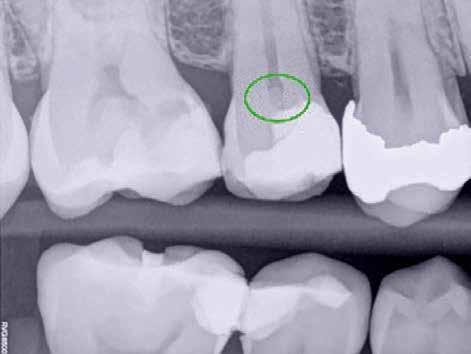

A radiológiai felvételek elemzése során a fog gyökércsúcsának megfelelően radiolucens elváltozást észleltünk, valamint a fognyak területének megfelelően szintén egy radiolucens területet figyelhettünk meg (1–2. ábra). Az elváltozások kiterjedésének és mélységének pontosabb meghatározása érdekében CBCT-felvétel készült (3. ábra). A felvétel alapján Heithersay-féle III. osztályú külső fognyaki gyökérfelszívódást diagnosztizáltunk (Heithersay Class III external cervical invasive root resorption; ECIR). Ezzel egyidejűleg pedig szimptomatikus periapikális periodontitis is fennállt. Ezt követően a pácienst a vizsgálati eredményekről, a kezelési alternatívákról és a várható prognózisról is tájékoztattuk.

A CBCT-felvételek rendkívül hasznos információkkal szolgálhatnak az endodonciai kezelések során. A felvételek segítségével meghatározhatjuk a külső fognyaki rezorptív lézió kiterjedését, felismerhetjük és osztályba sorolhatjuk az esetleges periapikális elváltozásokat, valamint nagyobb pontossággal felmérhetjük a fog belső anatómiai felépítését. Több szerző egymástól függetlenül is igazolta, hogy a CBCT rendkívül hasznos eszköz a rezorptív léziók diagnosztizálása során.

3. a–d ábra: A koronális síkú metszeten jól megfigyelhető a lézió mesio-distalis kiterjedése (a), a szaggitális síkú metszet a lézió vesztibulo-orális nagyságát mutatja (b), a gyökércsúcs körül elhelyezkedő lézió a 3 dimenziós rekonstrukciós képen és a mesio-disztális irányú metszeten is jól megfigyelhető (c–d).

A cikkekben bemutatott esetnél a kezelésre szoruló fog gyökércsúcsánál periapikális lézió volt megfigyelhető és ezzel egyidejűleg külső fognyaki gyökérrezorpció is fennállt. A periapikális és a rezorptív lézió méretének pontos meghatározását és térbeli elhelyezkedésének vizsgálatát CBCT-felvétel segítségével végeztük.